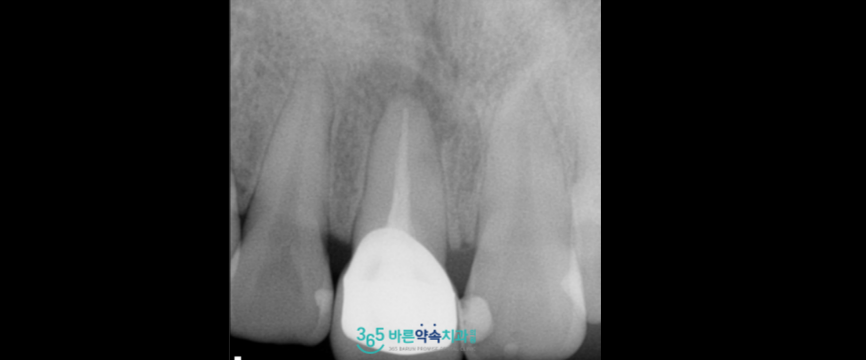

국소 마취 후

해당 부위의 잇몸을 절개하여

잇몸뼈와 치근단 주변에 있는

감염된 부위와 염증 조직을

깨끗하게 제거하였으며,

염증이 있었던 뿌리 끝을

약 2~3mm 정도 잘라낸 뒤

그 부위를 생체 적합 재료인

MTA로 역방향 충전을 시행하여

단단하게 밀봉하였는데요.

MTA는

항균성과 밀폐력이 뛰어나

감염 차단에 효과적이며

생체적합성이 높아

주변 조직의 염증 반응을 최소화하고

조직 재생까지 유도하기 때문에

치아를 살릴 수 있는 가능성을 높이는데

중요한 역할을 하는 치과 재료입니다.

치근단 절제 이후

주변에 뼈이식재를 넣어

빈 공간을 메워드리면서

봉합 후 치료를 마무리해 드렸습니다.